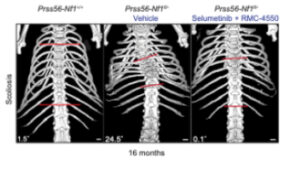

The article “Pharmacological inhibition of RAS pathway alleviates spine deformity in a mouse model of neurofibromatosis type 1” was published in Bone Research, 2025 Dec 16;13(1):103, by Kovaci F, Goachet C, Perrin S, Slimani L, Coulpier F, Tilotta F, Topilko P, Colnot C. DOI: 10.1038/s41413-025-00492-3

In this article, we investigated spinal deformities in the Prss56-Nf1 KO mouse model of neurofibromatosis type 1 (NF1). This is the first NF1 mouse model that recapitulates spinal deformity, along with other NF1 symptoms, providing a clinically relevant model for developing new therapeutic applications. We showed that treating Nf1-KO mice with RAS-MAPK pathway inhibitors prevented spine deformity, highlighting a promising therapeutic strategy for preventing NF1 spine deformity.